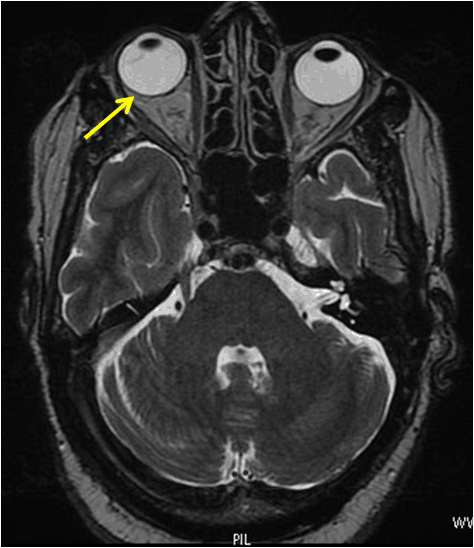

A 63-year-old man presented with blurred vision and a progressive loss of visual acuity for approximately two weeks. Medical history was remarkable for infiltrating breast carcinoma with negative complete work-up, for which he has had mastectomy, radiation therapy and chemotherapy in 2009. Ophthalmic examination showed exophthalmos of the right eye without ptosis. Ocular motility was normal. Best corrected visual acuity was (BCVA) 3/10 on the right eye and 7/10 on the left eye. Anterior segment examination was normal on both eyes with no dense cataracts observed. Fundoscopy under pupil dilatation in the right eye revealed an ill-defined choroidal mass in the upper temporal arcade, impinging on the macula and surrounding the papilla. The mass was associated with pigment epithelium impairment and normal optic discs, without macular edema. Fundoscopy in the left eye did not reveal any tumor. Standardized B-scan ultrasonography of the right eye revealed a posterior, hyperechogenic tumor of the choroid with secondary retinal detachment associated with choroidal thickening (Figure 1). Indocyanine green chorioangiography (ICG) was unremarkable in the left eye, but revealed a tumor in the right eye (Figures 2, 3). Magnetic resonance imaging (MRI) revealed a right ocular expansive lesion with non-circumferential posterior choroidal thickening (Figure 4).

Figure 4: Axial MRI (T2-weighted) revealed a choroidal mass in the right eye (arrow).